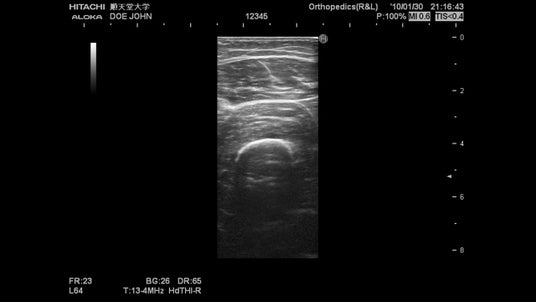

1.順天堂大学の研究員が、エコーを用いて、参加者の太ももの筋肉の画像を撮像します!

2.計測が終わった後は、結果を、オリンピアンや、他の参加者と見比べてみましょう!

大学のスタッフの説明を受けながら自身の超音波画像を観察することで、人の体の構造に関する知識を深めることができます。

また実際に参加者自身に厚さ計測を体験してもらうことで、計測を正確に行うために必要な知識(再現性など)を学ぶことができます。